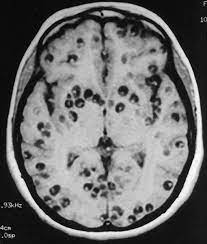

El caso de un joven atendido por fuertes dolores de cabeza y convulsiones reveló una enfermedad conocida como neurocisticercosis, provocada por larvas del parásito Taenia solium.

Estas larvas se alojan en el cerebro, causando inflamación, daño neuronal y, en casos graves, convulsiones o la muerte.